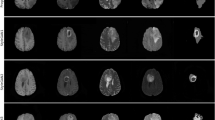

To evaluate the sample realism, we trained the models on all of the available data and, where possible, we sampled in a controlled manner. The synthetic datasets had the same number of samples as their real counterparts to guarantee a fair comparison. As shown in Table 1, the proposed model outperformed all of the baselines by a wide margin, ranging up to two orders of magnitude in the case of FID and MMD. The diversity measured by the MS-SSIM and 4-G-SSIM was roughly the same. This should be considered together with the poor image sampling quality displayed in Extended Data Fig. 1 and Fig. 2 for other baselines. Altogether, our model generated sharper images that better adhere to the dataset’s underlying distribution. The HA-GAN sampling quality came closest to the proposed models, but it had apparent artefacts within the white matter, which did not align with the real morphology as showcased in the ‘Morphological evaluation’ section. While LS-GAN provided better FID than CCE-GAN, it lacked distribution alignment, as shown by the MMD. This discrepancy can be attributed to CCE-GAN working on 1283 downsampled space, which was then upsampled for quantitative metric calculations. Furthermore, manual inspection revealed that LS-GAN shows signs of mode collapse due to its reduced diversity in sampling compared with CCE-GAN.

Random synthetic samples from the LS-GAN, CCE-GAN and HA-GAN baseline trained on ADNI together with our proposed model trained on ADNI and the a real participant from the datasets. All three planes of visualization (axial, coronal and sagittal) are presented. Additionally an axial zoomed in visualization of the cerebellum is showcased due to the higher number of cortical folds entailing more high-frequency details. All the visualization planes are from the same synthetic samples and real participant.